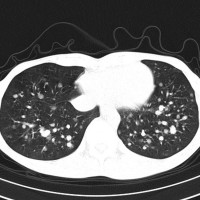

- でもきわめてまれに,頸静脈を介して肺転移します

- 髄膜腫の肺転移と同じような,ゆっくりとした進行という予後となります

- これは頸静脈を介してのこぼれ落ちるような肺転移です

- ですから,頸静脈を遮断するような腫瘍摘出手術をすれば予防できるという考え方もあります

多発性肺転移が発見され無治療で14年が経過しました。肺転移巣は無数ですがたいして増大しませんので普通の生活ができています。